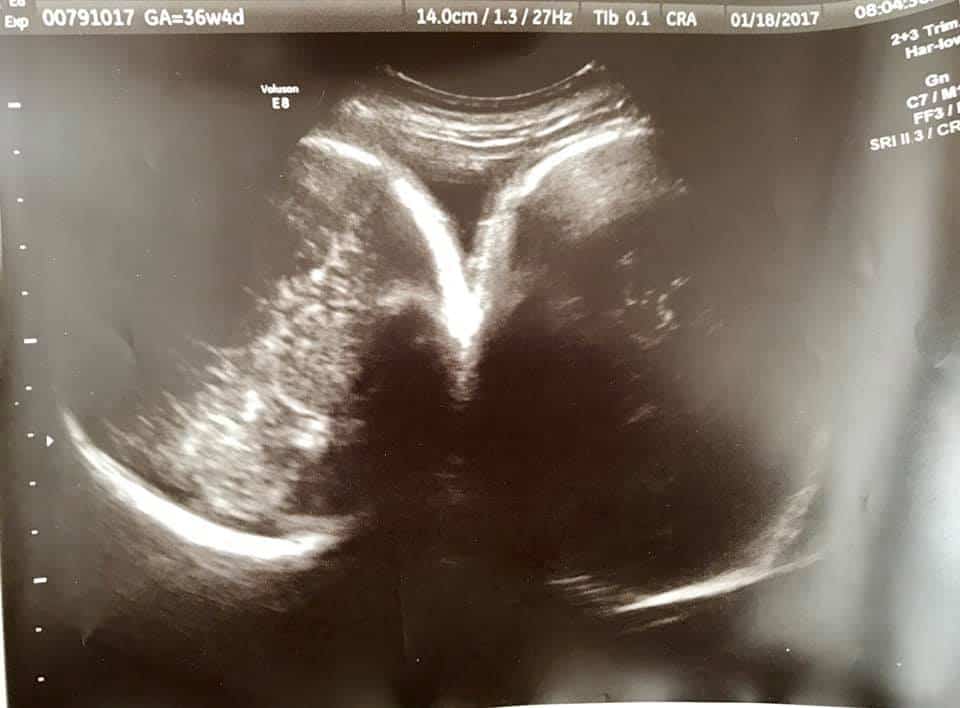

- Ultrasound Photos at 36 Weeks Pregnant With Twins

Ultrasound Photos at 36 Weeks Pregnant With Twins